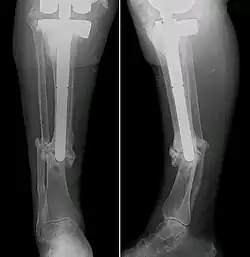

Intramedullary stabilization involves inserting a rod or nail into the tibial medullary canal. This offers structural support from within the affected bone, allowing for bone alignment and union. Surgeons may opt for flexible or rigid intramedullary nails depending on patient-specific factors such as age, pseudarthrosis severity and any accompanying deformities.[28] Although it almost guaranteed fracture healing and no refractures within a few years, the intramedullary nails would need to be replaced with age, leading to the pain of repeated surgery.[29][30][31]